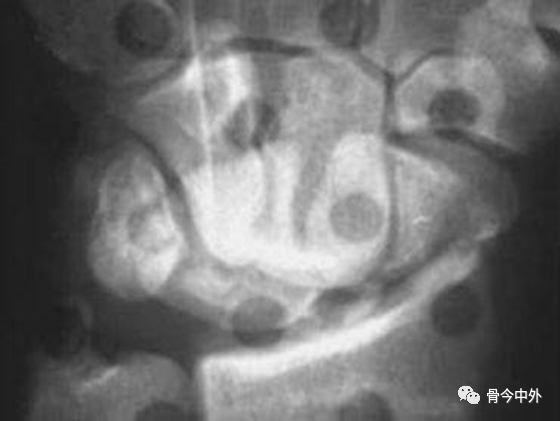

图21 左:月骨脱位;右:月骨周围脱位

月骨和月骨周围脱位:腕关节中立位置的背掌位和侧位X线片足以诊断月骨和月骨周围脱位。侧位像可以清晰显示在桡骨远端上方的月骨、头状骨和第三掌骨长轴呈直线状排列,这条线任何一点的中断都能确定半脱位或脱位的诊断。

当头状骨保持在直线上,一旦月骨成角度离开桡骨远端表面,月骨脱位即可被识别(图22A)。

同样的,在背掌位投照时,由舟骨远端凹面、月骨、三角骨所构成的弧线 II 的中断和相伴随的月骨三角形外观也可以诊断月骨脱位(图22B), 月骨脱位也能有效地从CT上显示,尤其是3D CT的重建图像(图23)。

图22 月骨脱位。(A)在腕关节侧位像上,月骨脱位时脱离由第三掌骨、头状骨和桡骨远端的长轴排列,月骨向掌侧旋转和移位。(B)背掌位投照显示弧线 II 在月骨位置中断。注意月骨的三角形外观及月骨脱位的征象。